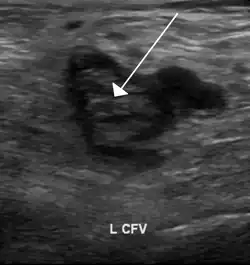

| Método de diagnóstico | Ecografia[1] |

Os indivíduos suspeitos de ter TVP podem ser avaliados usando uma escala de avaliação clínica como a escala de Wells.[2][3] Um exame de dímero D pode ser usado para assistir o diagnóstico diferencial ou para alertar para a necessidade de realizar mais exames.[1] O diagnóstico é geralmente confirmado com ecografia das veias suspeitas.[1] Em conjunto, a TVP e a embolia pulmonar são denominados trombose venosa.[1]

A trombose venosa profunda pode ser suspeitada através de achados do exame físico. Um sinal sugestivo da doença é o Sinal de Homan. Os exames confirmatórios de TVP incluem o ecodoppler venoso dos membros inferiores, análise do dímero D e angiografia.[10]